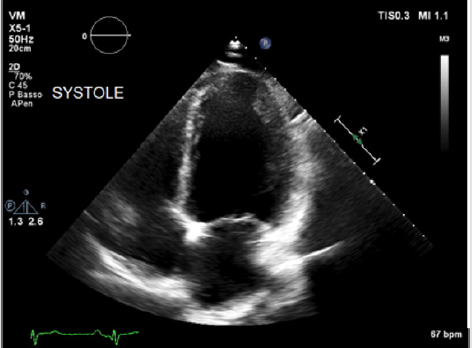

Physical examination showed a muscular man, the apex beat was not evident, the jugular at baseline showed an absent X’ descent with a positive hepato-jugular reflux and heart sounds were regular at the auscultation ; there was also minimal ankle swelling and , bilateral basal crackling rattles were audible at lung auscultation. The ECG showed a sinus rhythm with a frequency of 88 bpm, signs of left atrial enlargement, a left axial deviation and negative T-waves on D1 and aVL and from V4 to V6; no previous recent ECG was available for comparison. Chest X-ray showed pulmonary edema and an acute bronchopneumonia focus. Transthoracic echocardiography (TTE) revealed a dilated cardiomyopathy with severe left ventricular systolic dysfunction (LVEF 23% calculated with the Simpson biplane method) and dilatation (telediastolic diameter 79 mm) with moderate uniform hypertrophy (Figure 1a & 1b). There was grade II diastolic dysfunction (E/A waves ratio 1,9; E wave deceleration time 144 msec), “B-bump” on M-mode examination at the mitral valve level and an average E/e’ at tissue doppler analysis at the upper limit of the “grey zone”: 14 (Figure 2a-2d); global longitudinal peak systolic strain (GLPSS) was -7,4%; the left atrium was dilated; the right ventricle was dilated, slightly hypocontractile (tricuspidal annular plane systolic excursion, TAPSE, 16 mm) with a dilated right atrium; the inferior cava vein showed a normal dimension and collapsibility.

Figure 1a: Transthoracic echocardiography in the acute phase showing significant left ventricular dilatation (EDV 269 ml) and systolic dysfunction (LVEF 23% calculated with the Simpson biplane method): apical 4-chamber views in telediastole.